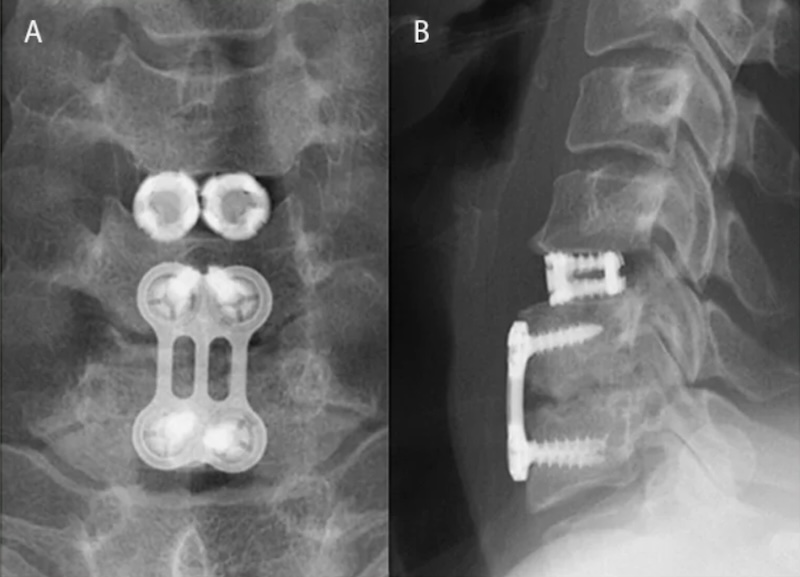

VariLift-C Cervical Stand-alone Expandable Threaded ACDF Spacer

The VariLift-C is a Cervical Expandable Titanium spacer for use in the ACDF procedure and approved for use in the single level either with or without supplemental fixation and used singly or bilaterally. The cage has an external threads with large fenestrations for graft. The expansion plate expands the central core.

Configuration: Cage Alone , 0-Profile (Integrated screws)

Expansion: Expandable , Bi-Directional Expansion